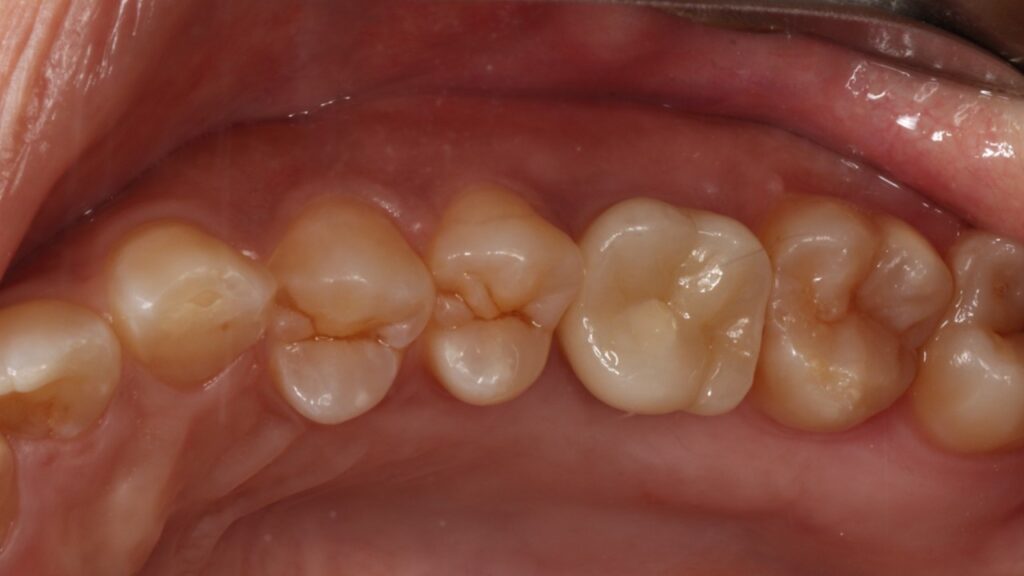

治療後

4ヵ月で最終的なセラミック冠を装着しています。

歯が割れた原因は無意識の噛みしめや歯ぎしりなので、就寝時にマウスピースを使うなどの対応もしています。